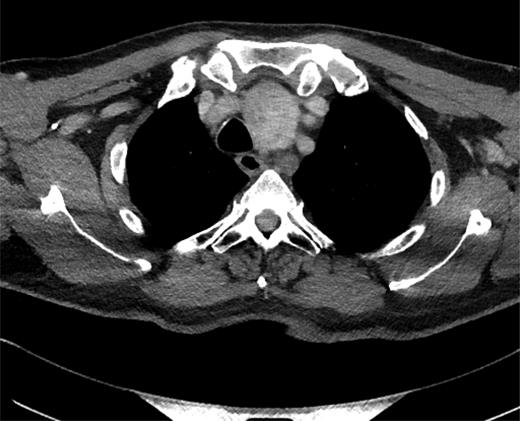

Thyroid function tests were normal. He underwent a computed tomographic (CT) scan of the neck and chest (Figs 1–3). It showed a large multinodular goitre with retrosternal extension of the left lobe to the arch of the aorta. The trachea was deviated to the right. Paraoesophageal swellings were noted in the upper posterior mediastinum, the largest of which measured 2 cm. These were non-enhancing masses, with no evidence of haemorrhage. The case was reviewed in a multidisciplinary meeting to exclude the differential diagnosis of necrotic paraoesphageal lymph nodes. The oesophagus was unremarkable, with no thickening or air-fluid level. In view of this and the continuity of the swellings with the thoracic duct, no further investigation or biopsy was undertaken.

Sagittal CT image showing a thyroid goitre with retrosternal extension and paraoesophageal swellings.